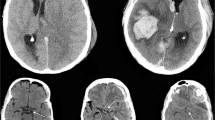

This prospective controlled cohort study enrolled a convenience sample adult patients (>18 years of age) with closed head injuries with a GCS score of <8. From March 2007–August 2011, patients were enrolled at two Level 1 trauma centers in Gainesville, Florida (Shands Hospital, University of Florida) and Houston, Texas (Ben Taub General Hospital, Baylor College of Medicine). Patients met inclusion criteria if they were ≥18 years old with a non-penetrating head injury and had a GCS <8 requiring the placement of an intraventricular catheter (IVC). Patients were excluded if they had a history of pre-existing end-stage organ disease or severe psychiatric illness. All patients had a computerized tomography (CT) scan done as part of their routine evaluation per hospital protocol.

Cerebrospinal fluid samples were obtained within 24 h of admission at 6, 12, 18, and 24 h post-injury by collection from the IVC reservoir that had been emptied 1 h prior to collection. Samples were then stored on ice for up to 12 h before being centrifuged and frozen at −80 °C as 1 ml serum aliquots for future analysis at Banyan Biomarkers Inc. (Alachua, FL, USA). The initial CT scan performed in the emergency department for each patient was reviewed by a single board certified neuroradiologist blinded to the patient’s clinical examination and outcome. The principal scoring system used in the CT interpretation was the Rotterdam Score [36]. The Rotterdam CT score was developed for prognostic purposes in TBI to determine the risk for mortality. It is based on CT findings of basal cistern compression, midline shift, presence of an epidural hematoma, and the presence of either intraventricular blood and/or traumatic subarachnoid hemorrhage. The primary outcome measure was mortality at 6 months post-injury. Because patients were unconscious upon eligibility determination, a 24-h waiver of consent was granted by the IRB. If informed consent could not be obtained from the patient’s legally authorized representative within 24 h, samples were discarded and the patient withdrawn from the study. Control subjects were patients without TBI (n = 21) requiring CSF drainage for other medical conditions such as for routine anesthetic or surgical management (e.g. endovascular aortic aneurysm stent repair, selected orthopedic procedures) or chronic hydrocephalus. Based on our previous work with UCH-L1 [32], the minimum number of control patients required to detect a difference between control and TBI patients was 14 given a power a power of 80 % and a significance level (alpha) of 0.05.

Of the 131 TBI patients, 110 had CSF collected for biomarker analysis within 24 h of injury (Fig. 1). Thirty (27 %) patients did not survive to 6 months. Of these, 5 patients (17 %) died within 48 h of injury, fourteen (47 %) died between 48 h to a week, seven (23 %) died between 1-week and 1-month, and 4 patients (13 %) died between 1 to 3-months. No patients died between 3–6 months. Twenty one patients (70 %) of patients’ deaths were directly associated with their TBI and the other 9 (30 %) had concomitant injuries or complications that may have contributed to their deaths in addition to the TBI. Two patients (7 %) died of brain death, 4 (13 %) died of traumatic/cardiac arrest, 6 (20 %) died from TBI complications, 13 (43 %) remained in a vegetative state and/or had care withdrawn, and 5 (17 %) died from non-neurological complications. Initial levels of biomarkers drawn within 24 h of injury are compared in those who did and did not survive to 6 months (Fig. 2).